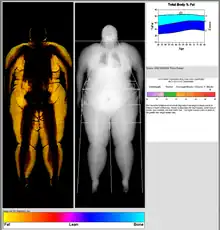

Body composition measurement

DXA scans can also be used to measure total body composition and fat content with a high degree of accuracy comparable to hydrostatic weighing with a few important caveats.[18] From the DXA scans, a low resolution "fat shadow" image can also be generated, which gives an overall impression of fat distribution throughout the body[19] It has been suggested that, while very accurately measuring minerals and lean soft tissue (LST), DXA may provide skewed results due to its method of indirectly calculating fat mass by subtracting it from the LST and/or body cell mass (BCM) that DXA actually measures.[20]

DXA scans have been suggested as useful tools to diagnose conditions with an abnormal fat distribution, such as familial partial lipodystrophy.[21][22][19] They are also used to assess adiposity in children, especially to conduct clinical research.[23]